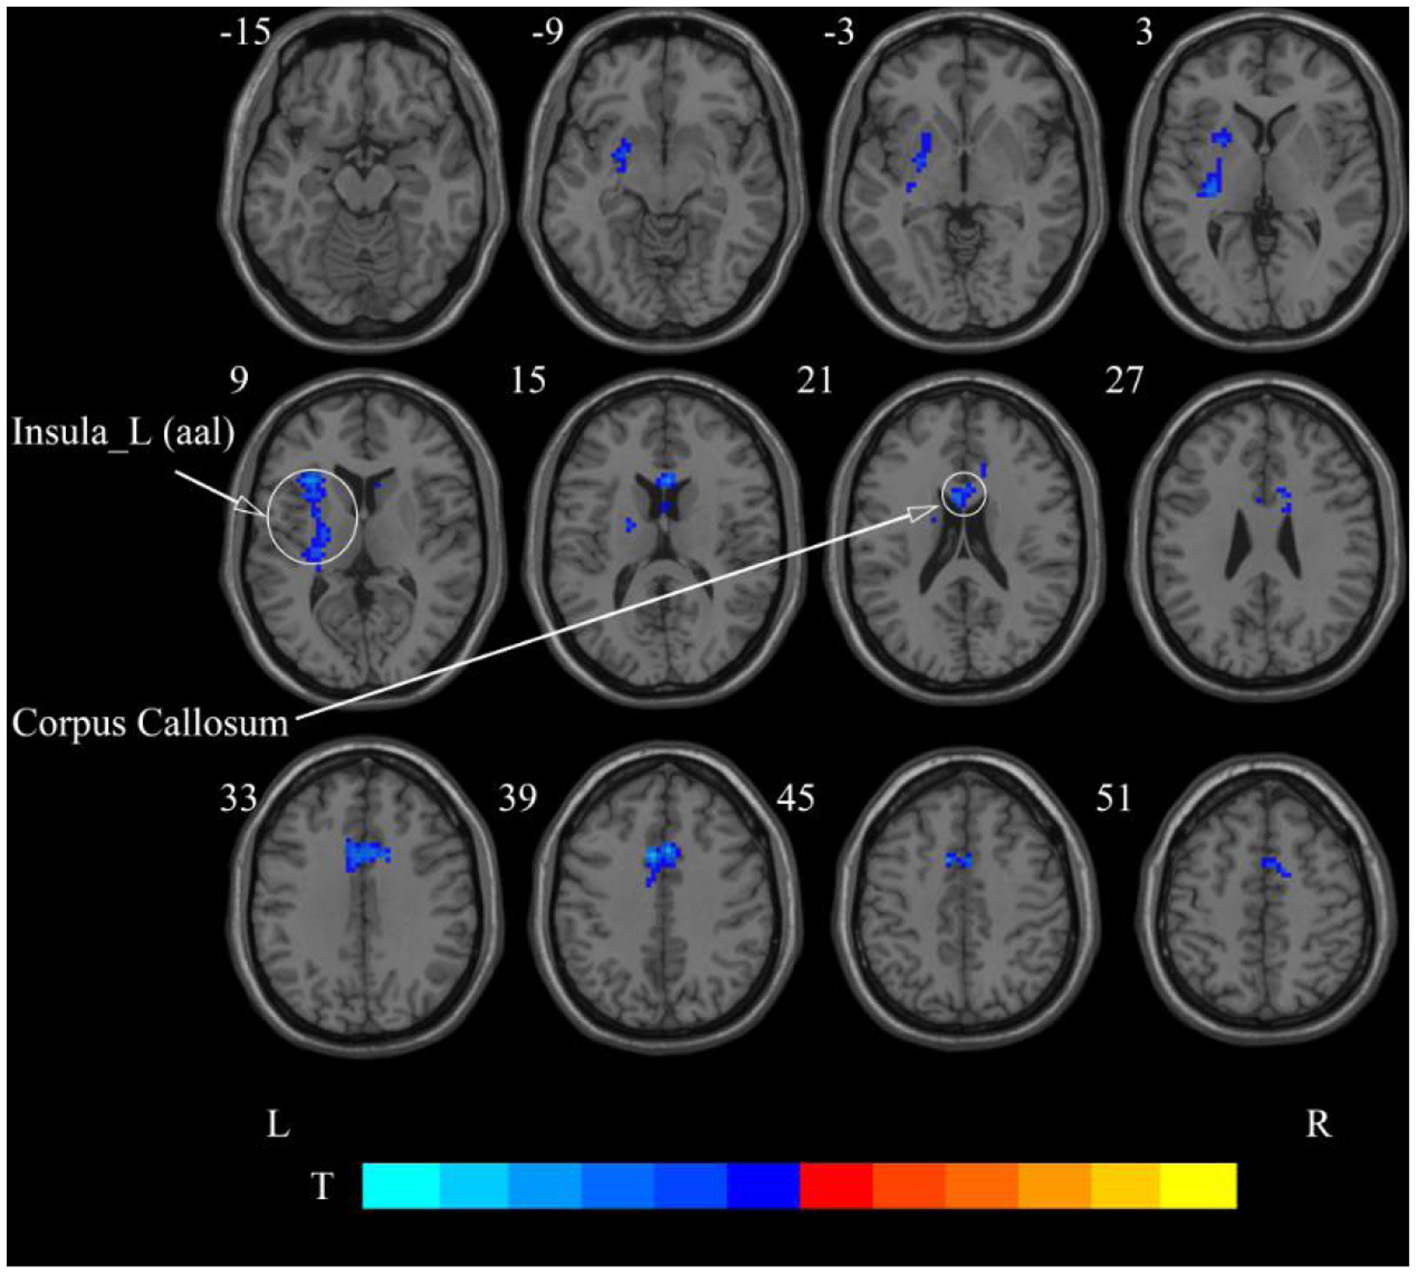

After cerebellar stimulation, in the classical frequency band we found significantly decreased ReHo at the left insula, right temporal lobe, and corpus callosum (p < 0.05; Figure 6 and Table 2). In addition, a decrease in ReHo was also found at the left insula and corpus callosum in the slow-4 band and at the right temporal lobe, left putamen, and left motor accessory area in the slow-5 band (p < 0.05; Figures 7, 8 and Table 2).

Figure 7. Statistical maps showing ReHo change pre- and post-rTMS in the slow-4 band. Cool colors showing ReHo decreased after rTMS p < 0.05.